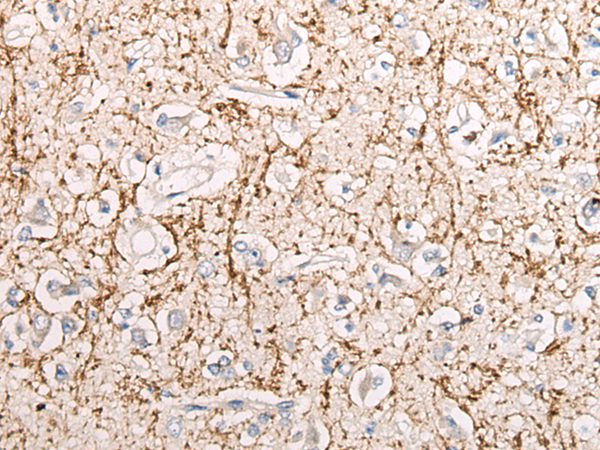

分类: 科研抗体货号: P05699别名: IBP2; IGF-BP53应用: IHC反应种属: Human, Mouse, Rat